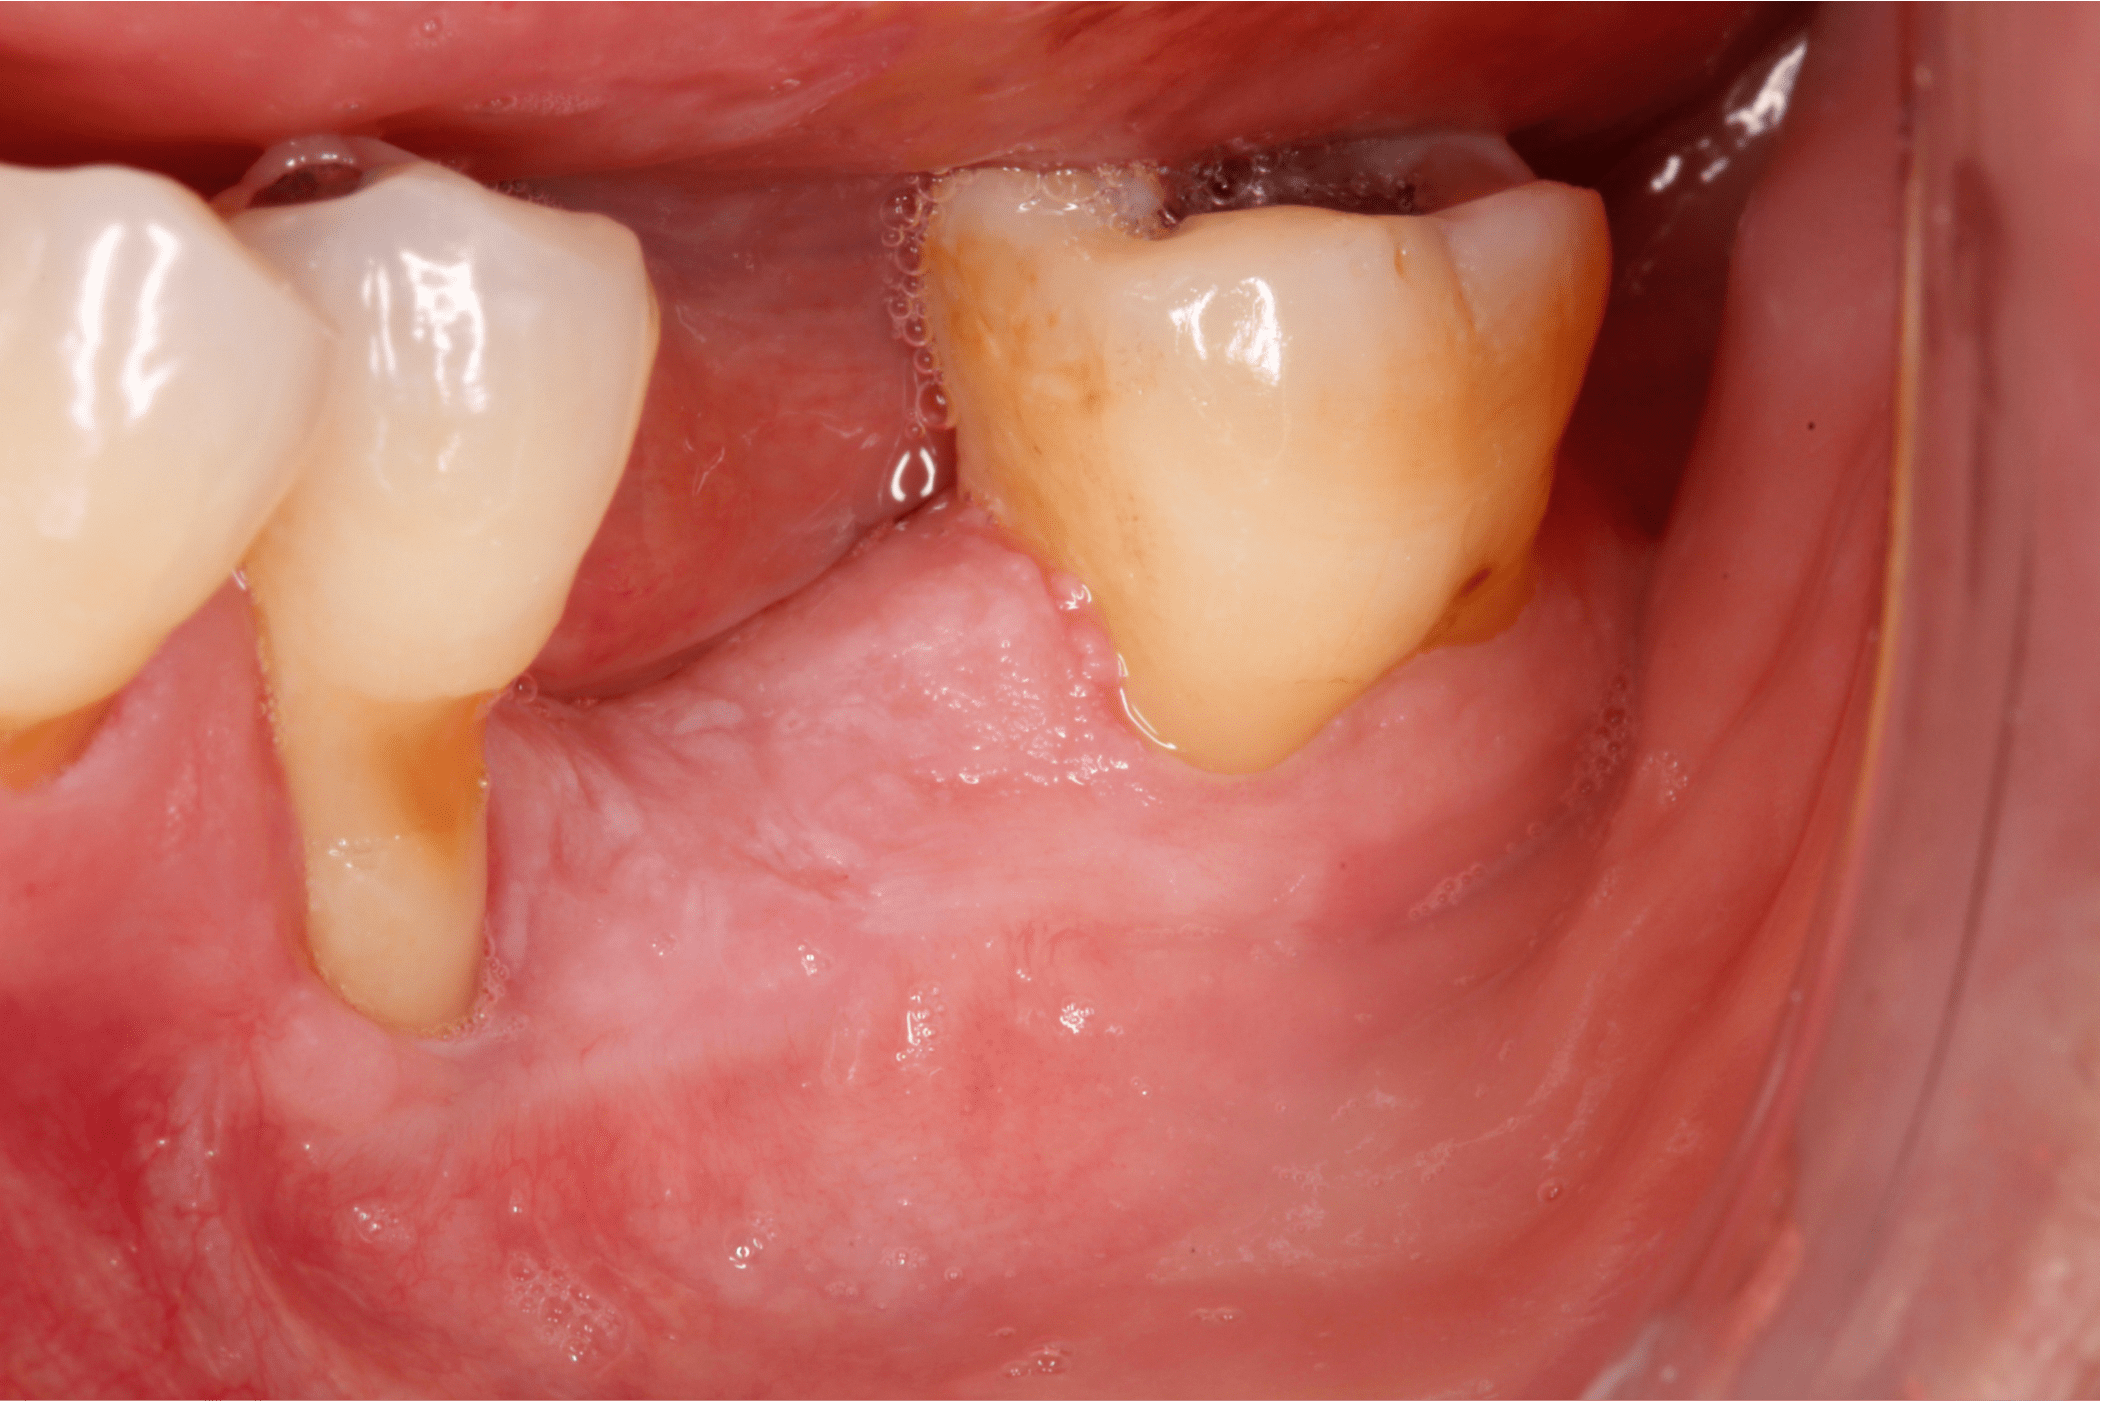

A los 45 días postoperatorio se puede observar la ganancia de encía queratinizada en la zona injertada, por lo que se planea la ROG una vez que el tejido blando se encuentre maduro, aproximadamente a los 3 meses (Fig.13).

Fig. 13